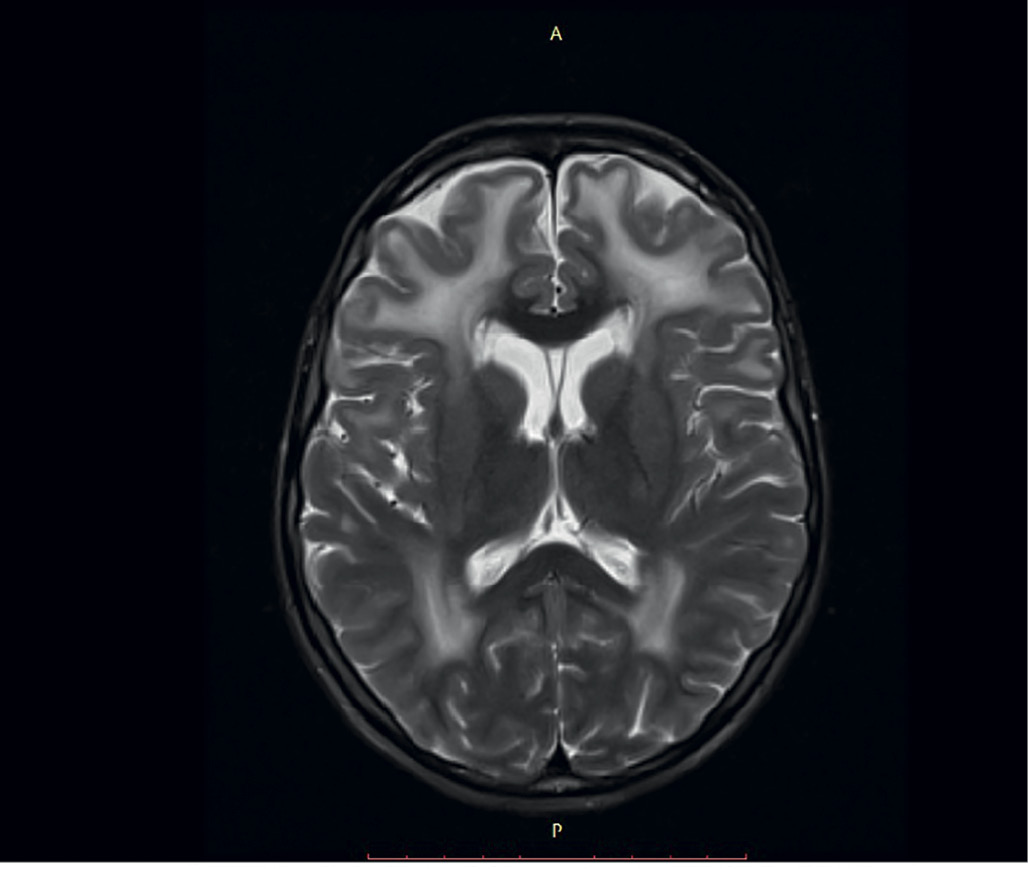

Важным диагностическим признаком МД-ВМД являются изменения на МРТ головного мозга в виде диффузного повышения сигнала от белого вещества в режимах Т2 и FLAIR (рис. 2). Эти проявления обусловлены увеличением содержания воды в белом веществе головного мозга в результате повышения проницаемости гематоэнцефалического барьера из-за дефицита ламинина-α2 в базальной мембране кровеносных сосудов головного мозга [19, 20]. Данные изменения обнаруживаются после 6 мес жизни ребенка (часто до 12 мес) и сохраняются на протяжении всей жизни [21]. Также в 4–5% случаев отмечаются структурные дефекты головного мозга в виде кортикальных дисплазий, полимикрогирии, агирии, пахигирии (чаще в затылочных отделах), гипоплазии ствола и/или мозжечка [6, 22].

Рис. 2. МРТ головного мозга.